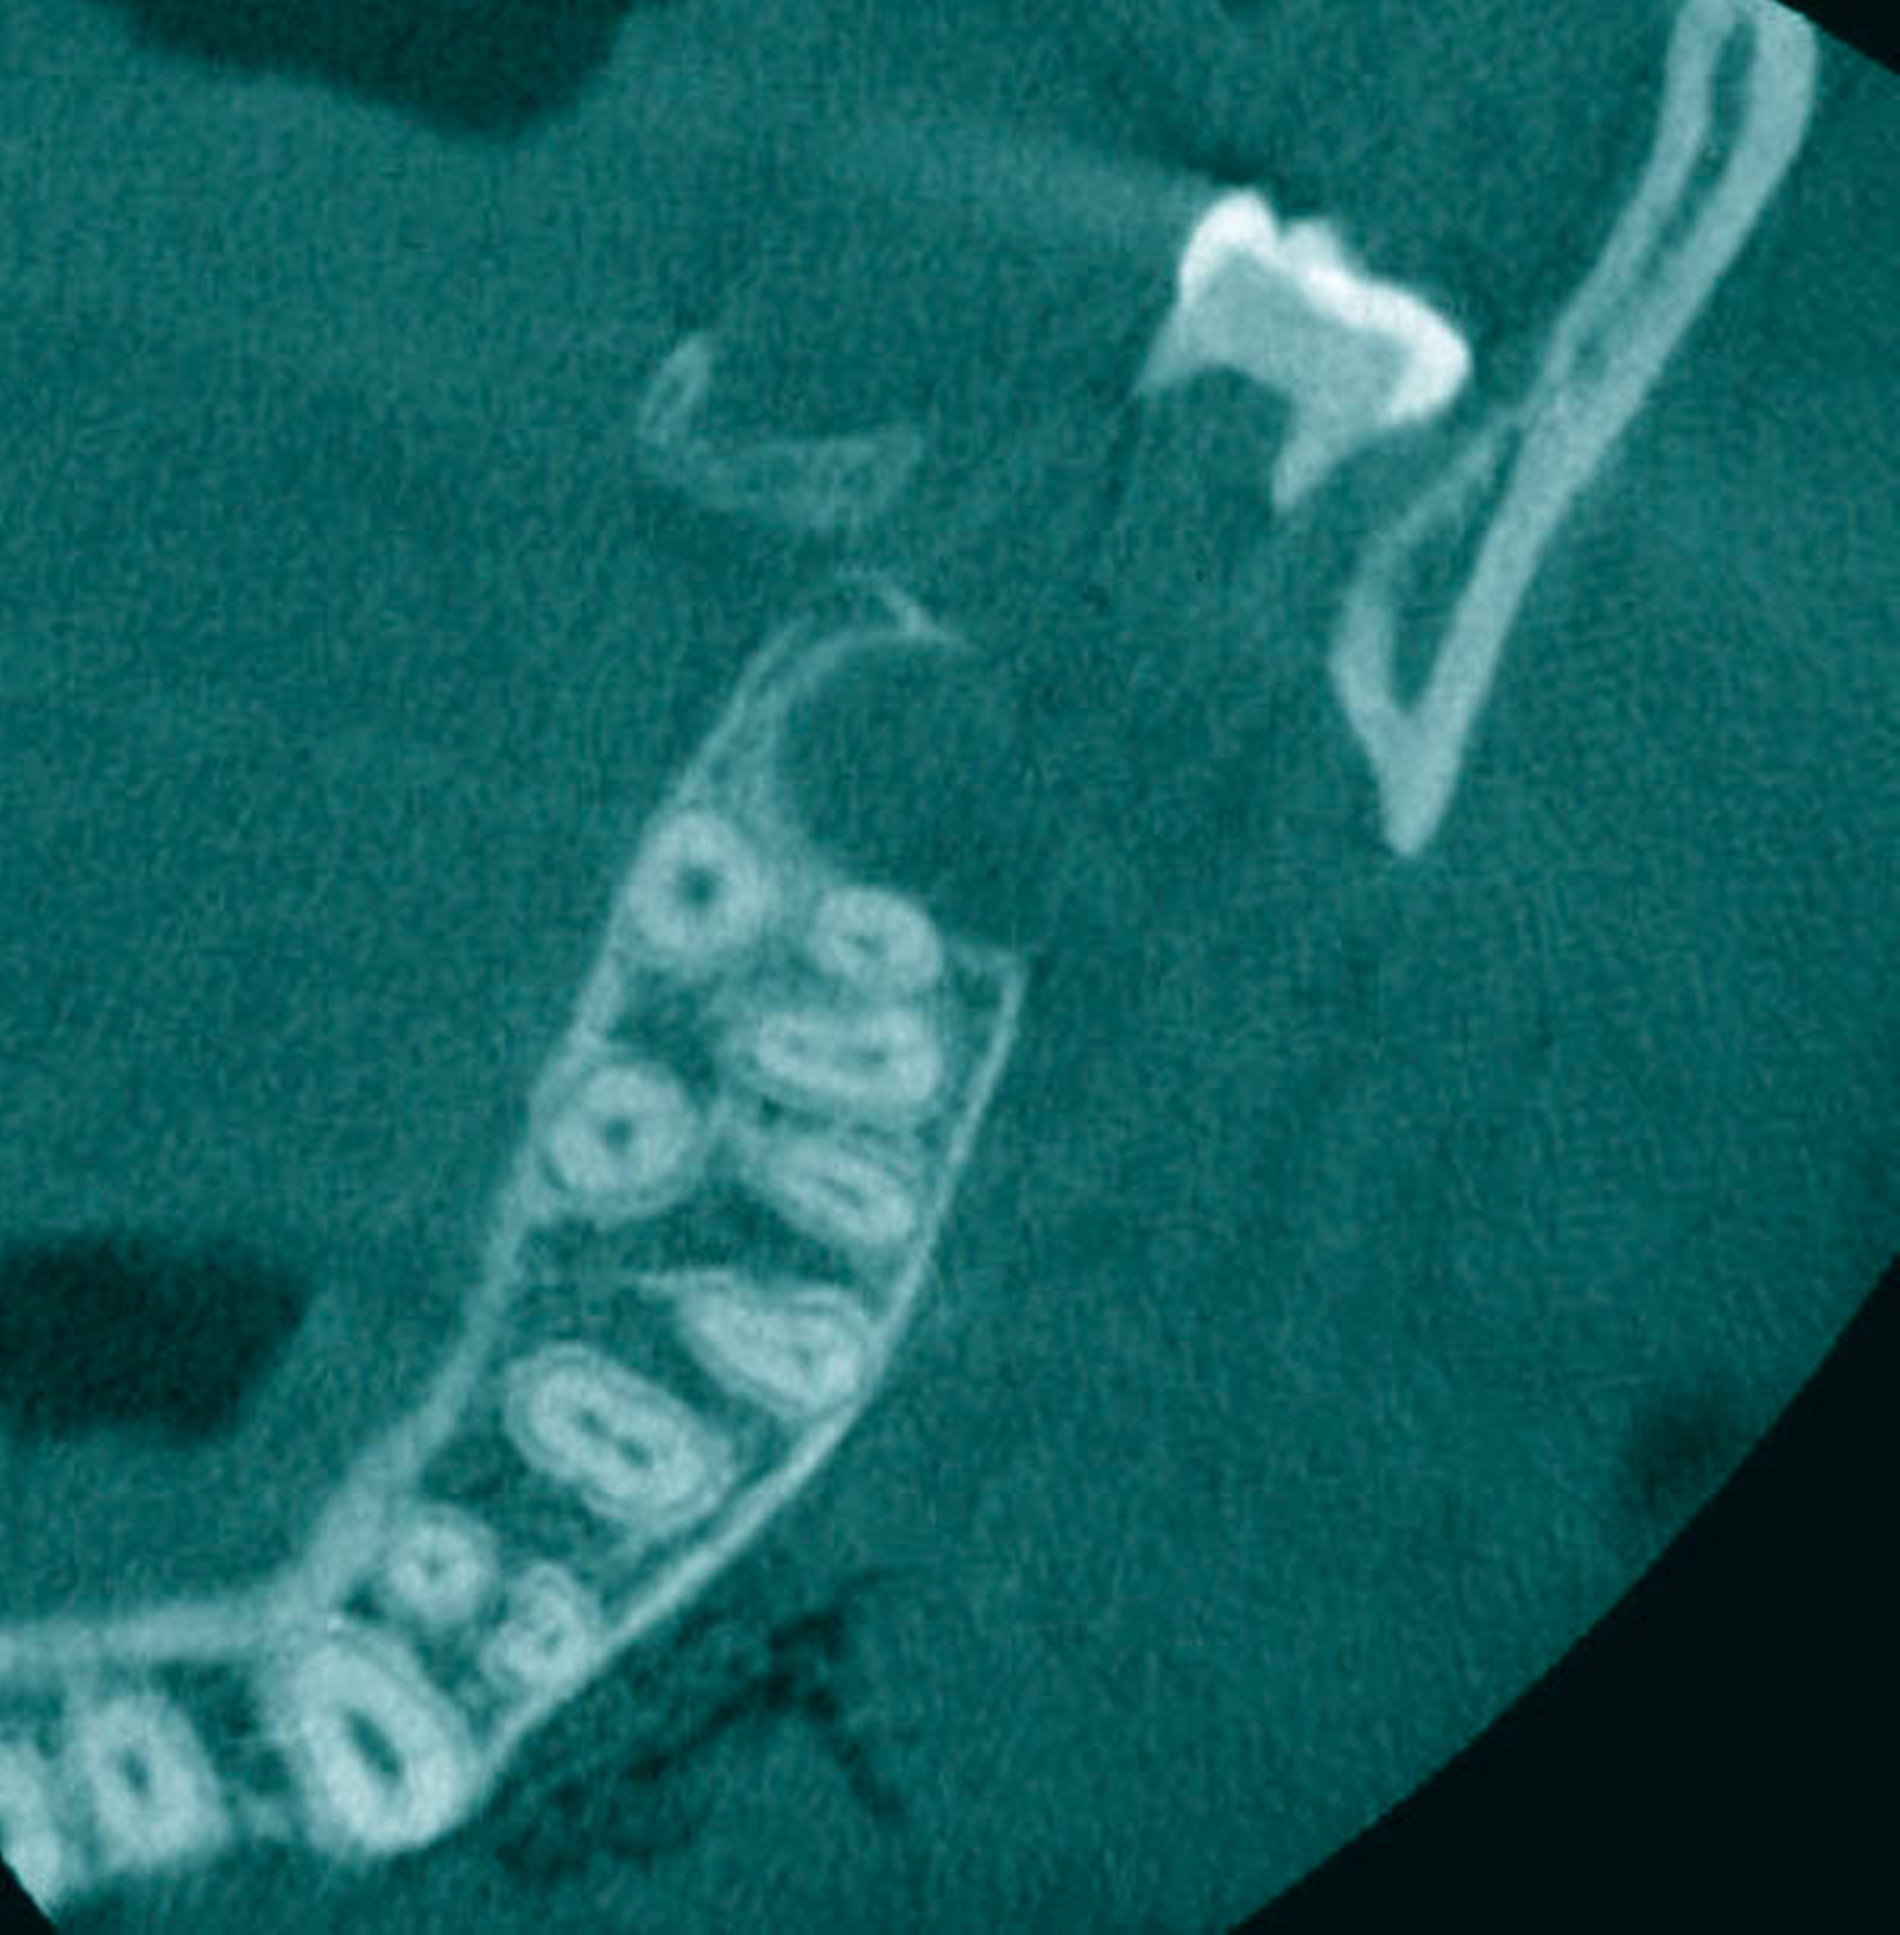

Ein 16-jähriger gesunder Patient stellte sich – überwiesen vom Vorbehandler – mit einem intraoperativ in das lingual gelegene Weichgewebe dislozierten Zahn 38 zur Therapieübernahme in der Klinik vor. Anamnestisch sollten aufgrund eines relativen Platzmangels alle Weisheitszähne entfernt werden (Abbildung 1). Der Eingriff war in einem zweizeitigen Vorgehen mit der Osteotomie je einer Kieferseite geplant gewesen. Nach der komplikationslosen Osteotomie des Zahns 28 wurde der Zahn 38 dargestellt. Dieser dislozierte im Verlauf der Entwicklung jedoch ins linguale Weichgewebe. Die sofortige Bergung scheiterte, woraufhin zur besseren Lokalisierung eine digitale Volumentomografie (DVT) angefertigt wurde. Hier zeigten sich eine hoch-mandibuläre Verlagerung nach lingual unterhalb des Nerveneintritts des N. alveolaris inferior sowie die Fraktur der lingualen Knochenlamelle (Abbildungen 2 und 3). Im Praxisumfeld war bei der gegebenen Dislokation eine sofortige Bergung nicht ohne ein erhöhtes Risiko der Nervschädigung möglich, so dass der Patient für eine Entfernung in Intubationsnarkose in die Klinik überwiesen wurde. Bei Aufnahme ließ sich eine Hypästhesie der linken Unterlippe und des Kinns sowie der linksseitigen Zungenspitze mit einer Einschränkung des Geschmacksinns nachweisen. Enoral zeigte sich eine reizfreie, frische Wunde im Bereich der linken Retromolar-Region im Oberkiefer und eine adaptierte reizfreie Wunde regio 37–38 im Unterkiefer.

Während für eine „Standard-Weisheitszahnosteotomie“ eine konventionelle Bildgebung ausreichend ist [Kunkel et al., 2013] sollte im Fall eines dislozierten Zahns eine radiologische Darstellung in mehreren Ebenen erfolgen, um eine sichere Lokalisierung und eine genaue Planung des chirurgischen Zugangs zur Bergung zu ermöglichen [Huang et al., 2007]. Ist eine DVT verfügbar, kann diese – wie im beschriebenen Fall – für eine genaue dreidimensionale Raumzuordnung erfolgen. Alternativ wird eine Bildgebung mittels Mundbodenübersicht/Panoramaschichtaufnahme oder mittels Computertomografie empfohlen [Huang et al., 2007].